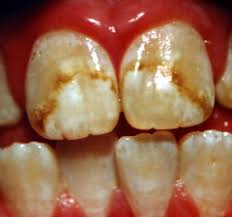

About 2 out of 5 adolescents have tooth streaking or spottiness because of too much fluoride, a government study found recently. In extreme cases, teeth can be pitted by the mineral — though many cases are so mild only dentists notice it. The problem is generally considered cosmetic and not a reason for serious concern.

The splotchy tooth condition, fluorosis, is unexpectedly common in youngsters ages 12 through 15 and appears to have grown more common since the 1980s, according to the Centers for Disease Control and Prevention.

A Severe Case of Dental Fluorosis